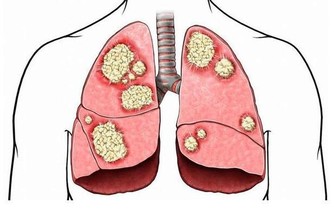

5.憋氣、口唇發紫:如果工作性質是久坐或長期站立,血液循環不好,

當病情發作時,除了疼痛外,

若還有憋氣、明顯的紫紺、口唇發紫、血氧下降等,就要高度懷疑可能是肺栓塞。

5.久坐:長期上網屬於靜態性動作,血液粘稠度較高,下肢可能形成深靜脈血栓,

運動時血栓脫落,可能會造成肺梗塞,嚴重可能導致猝死。